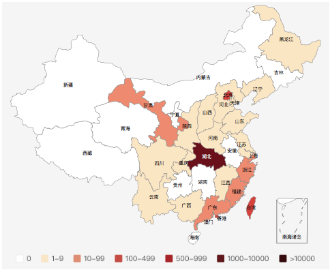

在与新冠病毒肺炎这场没有硝烟的战争中,科研是抗击疫情最核心的“武器制造机”。如果没有科学研究,我们难以想象在2个月内看到治愈人数快速增长,全国9个省份实现确诊人数“清零”(截止到3月23日),在这些数字的背后,科学研究毋庸置疑发挥了重要作用。因为我之前学习的是生物大类专业,再加上习惯对科研稍多一些留意,所以在关注疫情发展的同时,也简单梳理了一些科研抗“疫”的重要研究发现,希望对大家更科学的防疫抗疫有所帮助。

全国疫情地图(截止到3月23日)